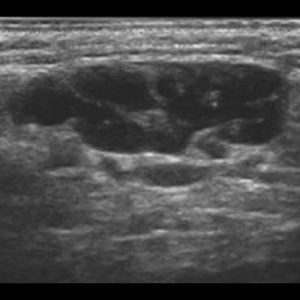

U tuyến nước bọt

Lượt xem: 170» 17-01-2021 -

U tuyến nước bọt

Lượt xem: 174» 17-01-2021 -

U tuyến nước bọt

Lượt xem: 149» 17-01-2021 -

U tuyến nước bọt

Lượt xem: 147» 17-01-2021 -